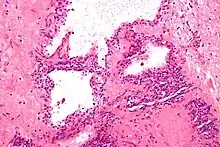

| Micrograph showing a pancreatic serous cystadenoma, a type of cystadenoma. H&E stain. | |